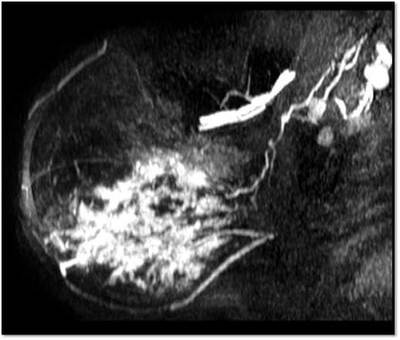

MG: Right breast shows focal asymmetric density in lateral quadrant extending for an area of 12.4 x 6.5 cm with no associated discrete mass or suspicious calcifications. Correlative ultrasound showed a heterogeneous area with echogenic vascular surrounding parenchyma in lateral quadrant with no discrete solid masses. MRI breast was performed on day 14 of LMP. Right breast shows an area predominantly consisting of fat in lateral quadrant extending for an area of 1.2×5.5x 8.9 cm along its maximum AP, ML and CC dimensions. This area is bright on fat suppressed T2 sequences and shows significant restriction on diffusion weighted sequences. There is rapid and progressive non mass enhancement in the above area extending anteriorly in to the nipple and posteriorly into the pectoralis major muscle. Two large and tortuous feeding vessels are seen to arise from the subclavian and axillary arteries respectively. Right breast shows predominantly fat containing mass showing abnormal enhancement described. The possibilities include vascular neoplasm or remotely fat necrosis. Ultrasound guided core biopsy was Suggestive of an inflammatory lesion, possibly fat necrosis. However enlarged and tortuous feeding arteries to the vascular mass was worrisome and we recommended an excision biopsy correlation. Excision biopsy showed “Multiple patchy areas of dense inflammatory infiltration in a background of fat necrosis”.